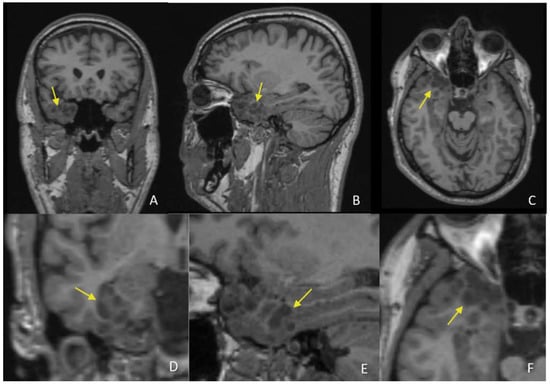

New Imaging Features of Multinodular and Vacuolating Neuronal Tumor Revealed by Alcohol and Illicit Drugs Consumption

Sirbu, C.A.; Ștefani, C.; Tuță, S.; Manole, A.M.; Sirbu, O.M.; Ivan, R.; Toma, G.S.; Calu, A.G.; Jianu, D.C. New Imaging Features of Multinodular and Vacuolating Neuronal Tumor Revealed by Alcohol and Illicit Drugs Consumption. Diagnostics 2022, 12, 2779. https://doi.org/10.3390/diagnostics12112779